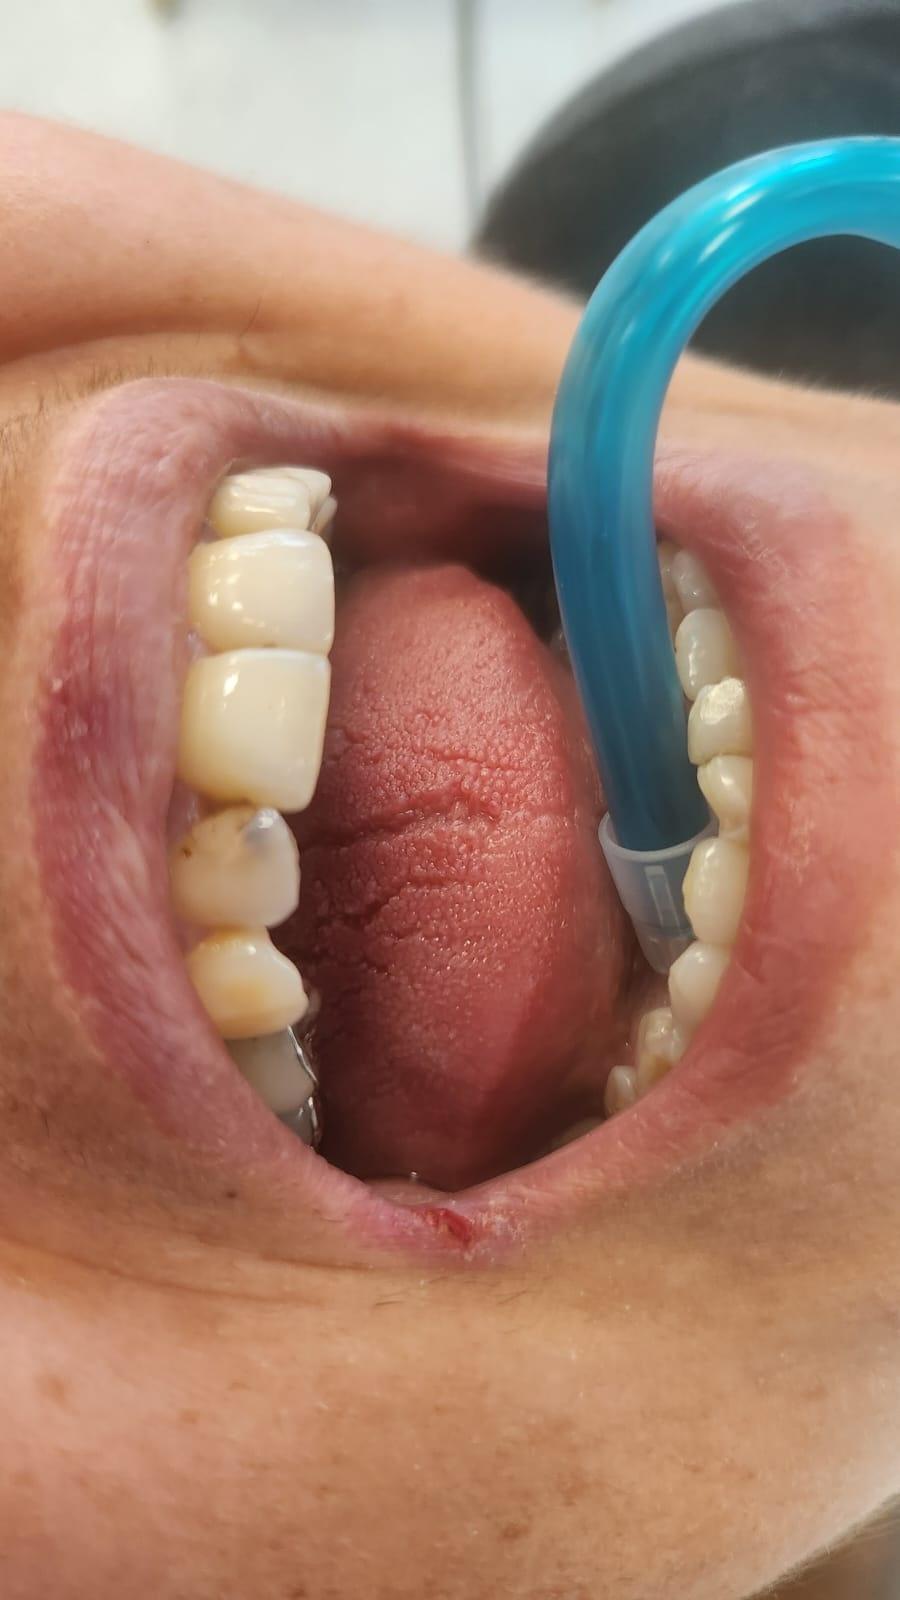

La Clinica LUY ESTHETIC ART se fac tratamente stomatologice pentru remedierea unui zambet perfect prin intermediul aparatului dentar. Pacientii au la dispozitie numeroase tipuri de aparate dentare, in functie de preferinte, necesitate si costuri. Pentru ca modificarile necesare sa se faca intr-un timp mai scurt, este necesara purtarea lui de la varste fragede, cand oasele nu sau dezvoltat complet.

Pot folosi aparate dentare si adultii, deoarece reprezinta cea mai buna varianta de indreptare a problemelor prezente la nivelul cavitatii orale, dar si de natura estetica. Medicul ortodont recomanda aparate dentare in urmatoarele cazuri: dinti strambi sau inghesuiti, dantura cu multe spatii, persoanele care au diastema (strungareata), dificultati la mestecarea alimentelor.

Exista mai multe tipuri de aparate denatare: metalic, ceramic, lingual (invizibil) etc.